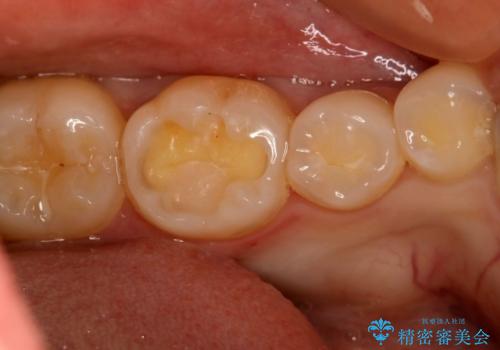

- 10年以上ぶりに歯科に来院された患者です。

口腔内・レントゲン写真からう蝕が見られたので治療を勧めたところ、自費治療を希望されたのでセラミックインレーにて治療を行いました。

左下6番のカリエス除去を行ったところ、深くまで削る必要があったため、CR裏層をした上でセラミックインレー形成をしました。